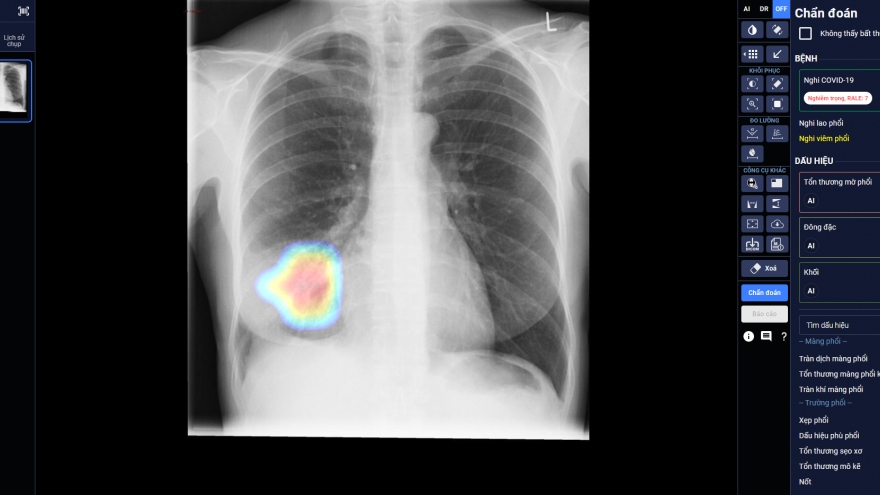

VOV.VN - Vài năm trở lại đây, trí tuệ nhân tạo (AI) trở thành chủ đề nóng tại Việt Nam. Phát kiến hiện được cho là thú vị nhất của nhân loại đang trở nên gần gũi với nhiều hoạt động sống thường ngày của người Việt, từ các lĩnh vực công nghệ, y tế, ngân hàng, giải trí, cho đến giao thông...